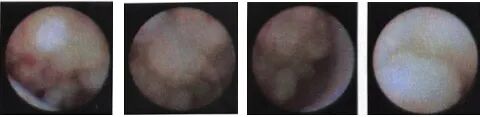

乳管镜下图像

正常乳管扩张

乳管炎症--一般炎症乳管炎症--出血性炎症

乳管内乳头状瘤

乳头状瘤病

导管内癌

浸润性导管癌